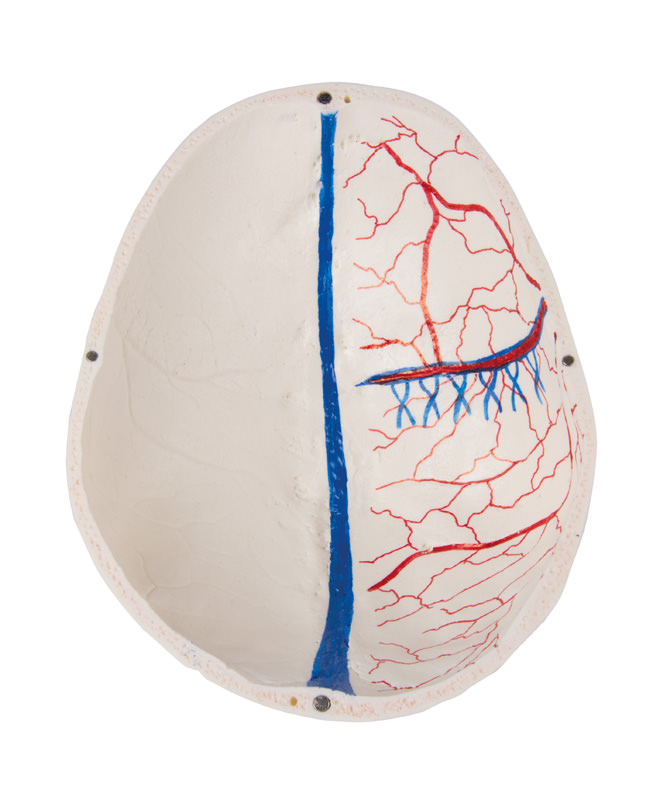

Das Schädeldach ist eröffnet und abnehmbar lässt aber die Schläfenbeine und ihre Nähte unberührt. Knöcherne Impressionen des sinus sagittalis, des sinus transversus und des sinus sigmoideus wie auch der Hirnhautgefäße sind bemalt. Die Schädelbasis ist sagittal geschnitten in der Form, dass der Schnitt auf einer Seite durch eine Siebplatte und ein weiterer Schnitt mit gleicher Ebene durch die andere Siebplatte des Siebbeins verläuft, was die Christa galli und die Lamina perpendicularis wie auch die ganze Nasenscheidewand intakt lässt. Die Strukturen der vorderen, mittleren und hinteren Schädelgrube sind einfach zugänglich. Man kann direkt die Nasenhöhle, die Nasenmuschel, das Septum sowie den knöchernen Rachenraum und Nasenrachenraum sehen. Die Nasenscheidewand kann aus den umgebenden Knochenstrukturen entnommen werden. Die Stirnhöhlen sind auf der einen Seite als Ganzes präpariert, auf der anderen Seite eröffnet, so dass sie voll zugänglich ist. Die Beziehung dieses Sinus zur Nasenhöhle ist klar zu erkennen, dies ist besonders wertvoll für HNO-Ärzte.